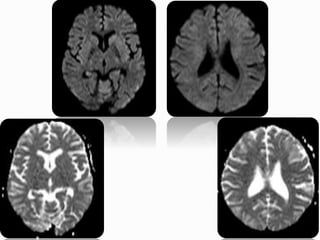

 21yr old female patient

 k/c/o SLE on steroids

 Presented with GTCS and Altered sensorium

Altered sensorium Case 2014

 Restricted diffusion (11-26%)

 Hemorrhage (10.5-17.1%) : parenchymal or

subarachnoid

 Altered brain perfusion : regional decreased or

increased, depends on disease time course